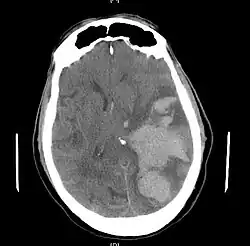

Brain herniation is a potentially deadly side effect of very high pressure within the skull that occurs when a part of the brain is squeezed across structures within the skull. The brain can shift across such structures as the falx cerebri, the tentorium cerebelli, and even through the foramen magnum (the hole in the base of the skull through which the spinal cord connects with the brain). Herniation can be caused by a number of factors that cause a mass effect and increase intracranial pressure (ICP): these include traumatic brain injury, intracranial hemorrhage, or brain tumor.[1]

Treatment involves removal of the etiologic mass and decompressive craniectomy. Brain herniation can cause severe disability or death. In fact, when herniation is visible on a CT scan, the prognosis for a meaningful recovery of neurological function is poor.[2] The patient may become paralyzed on the same side as the lesion causing the pressure, or damage to parts of the brain caused by herniation may cause paralysis on the side opposite the lesion.[11] Damage to the midbrain, which contains the reticular activating network which regulates consciousness, will result in coma.[11] Damage to the cardio-respiratory centers in the medulla oblongata will cause respiratory arrest and (secondarily) cardiac arrest.[11] Investigation is underway regarding the use of neuroprotective agents during the prolonged post-traumatic period of brain hypersensitivity associated with the syndrome.[17]